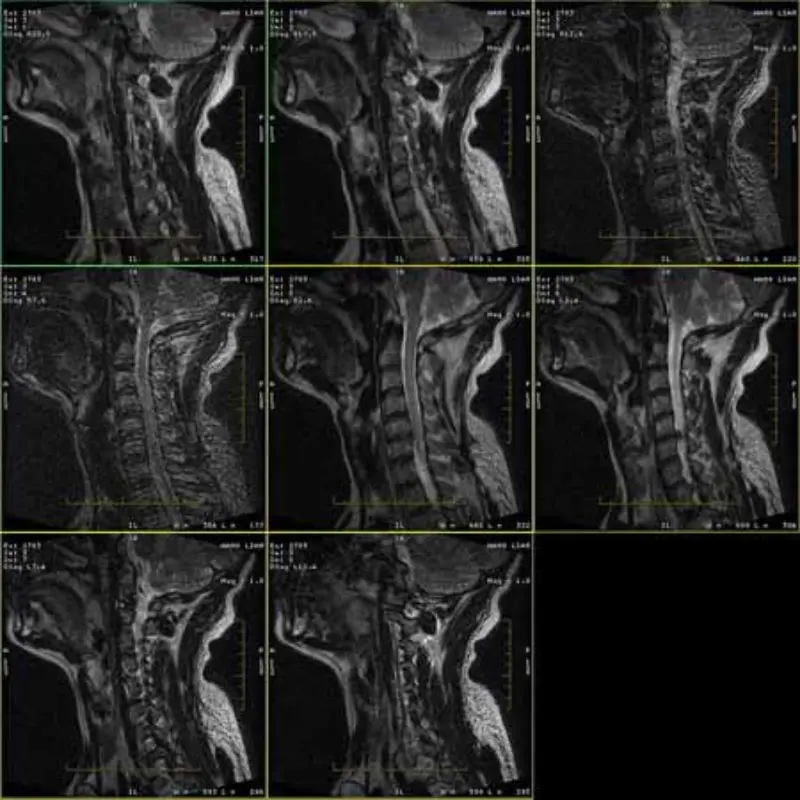

Tá taibhse ag íomhánna prótacail FRFSE agus GRE agus uaireanta tá íomhánna SNR íseal le feiceáil i sraith amháin. Ach tá íomhánna prótacal SE gnáth.

Féach íomhánna leis seo le do thoil.